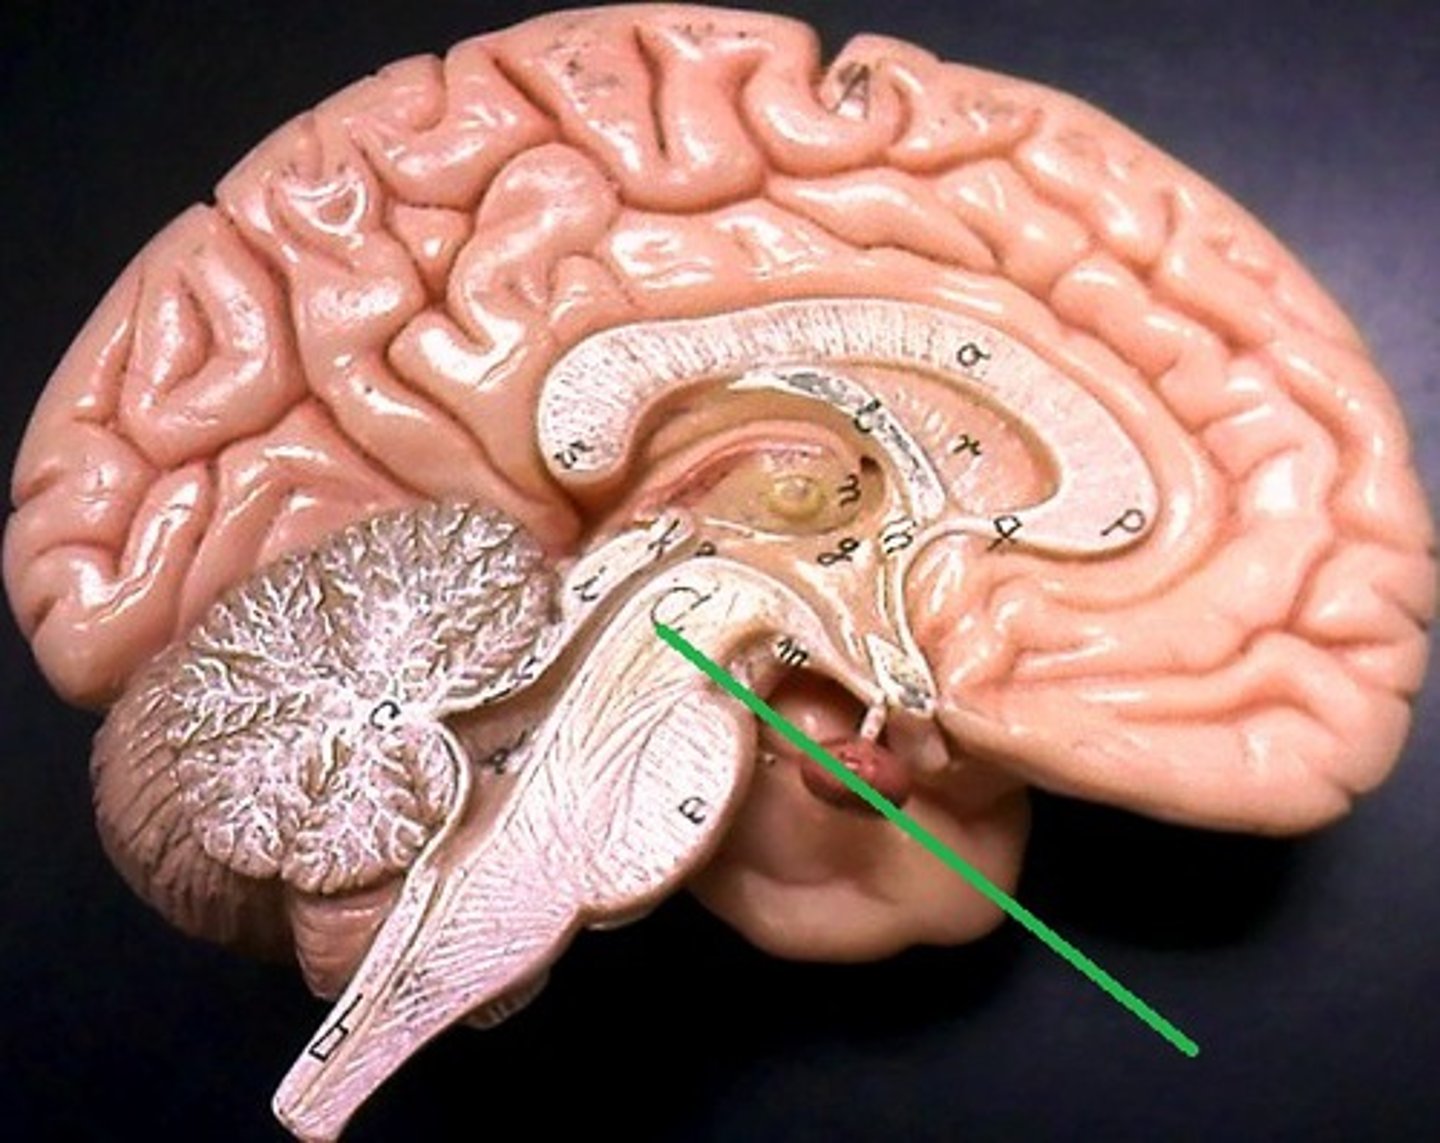

pineal body (pineal gland)

thalamus

hypothalamus

infundibulum

pituitary gland

mammillary bodies

midbrain (mesencephalon)

pons

medulla oblongata

cerebral aqueduct (mesencephalic aqueduct)

interventricular foramen